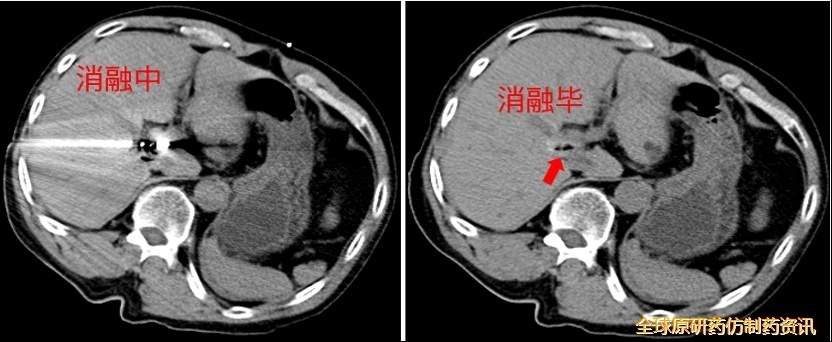

第四次消融(2021.07.28)

CT消融过程中,消融针从门-腔间隙穿透肿瘤;

消融毕,术区呈条状密度增高灶,相邻胆管、血管无扩张、积气。

图10 第四次消融示意图